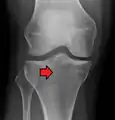

Lipohemarthrosis (presence of fat and blood from bone marrow in the joint space after an intraarticular fracture) seen on X-ray in a person with a subtle tibial plateau fracture

Lipohemarthrosis due to a tibial plateau fracture

Subtle tibial plateau fracture on an AP X ray of the knee